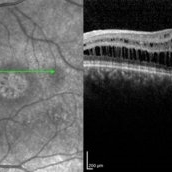

Best Disease Best DiseaseMar 9 2013 by Hamid Ahmadieh, MD OCT of the right eye of a 49-year-old man with decreased VA due to advanced Best disease. Photographer: Soodabeh Fooladin, Negah Eye Center, Tehran Imaging device: Heidelberg Spectralis Condition/keywords: Best disease, optical coherence tomography (OCT)